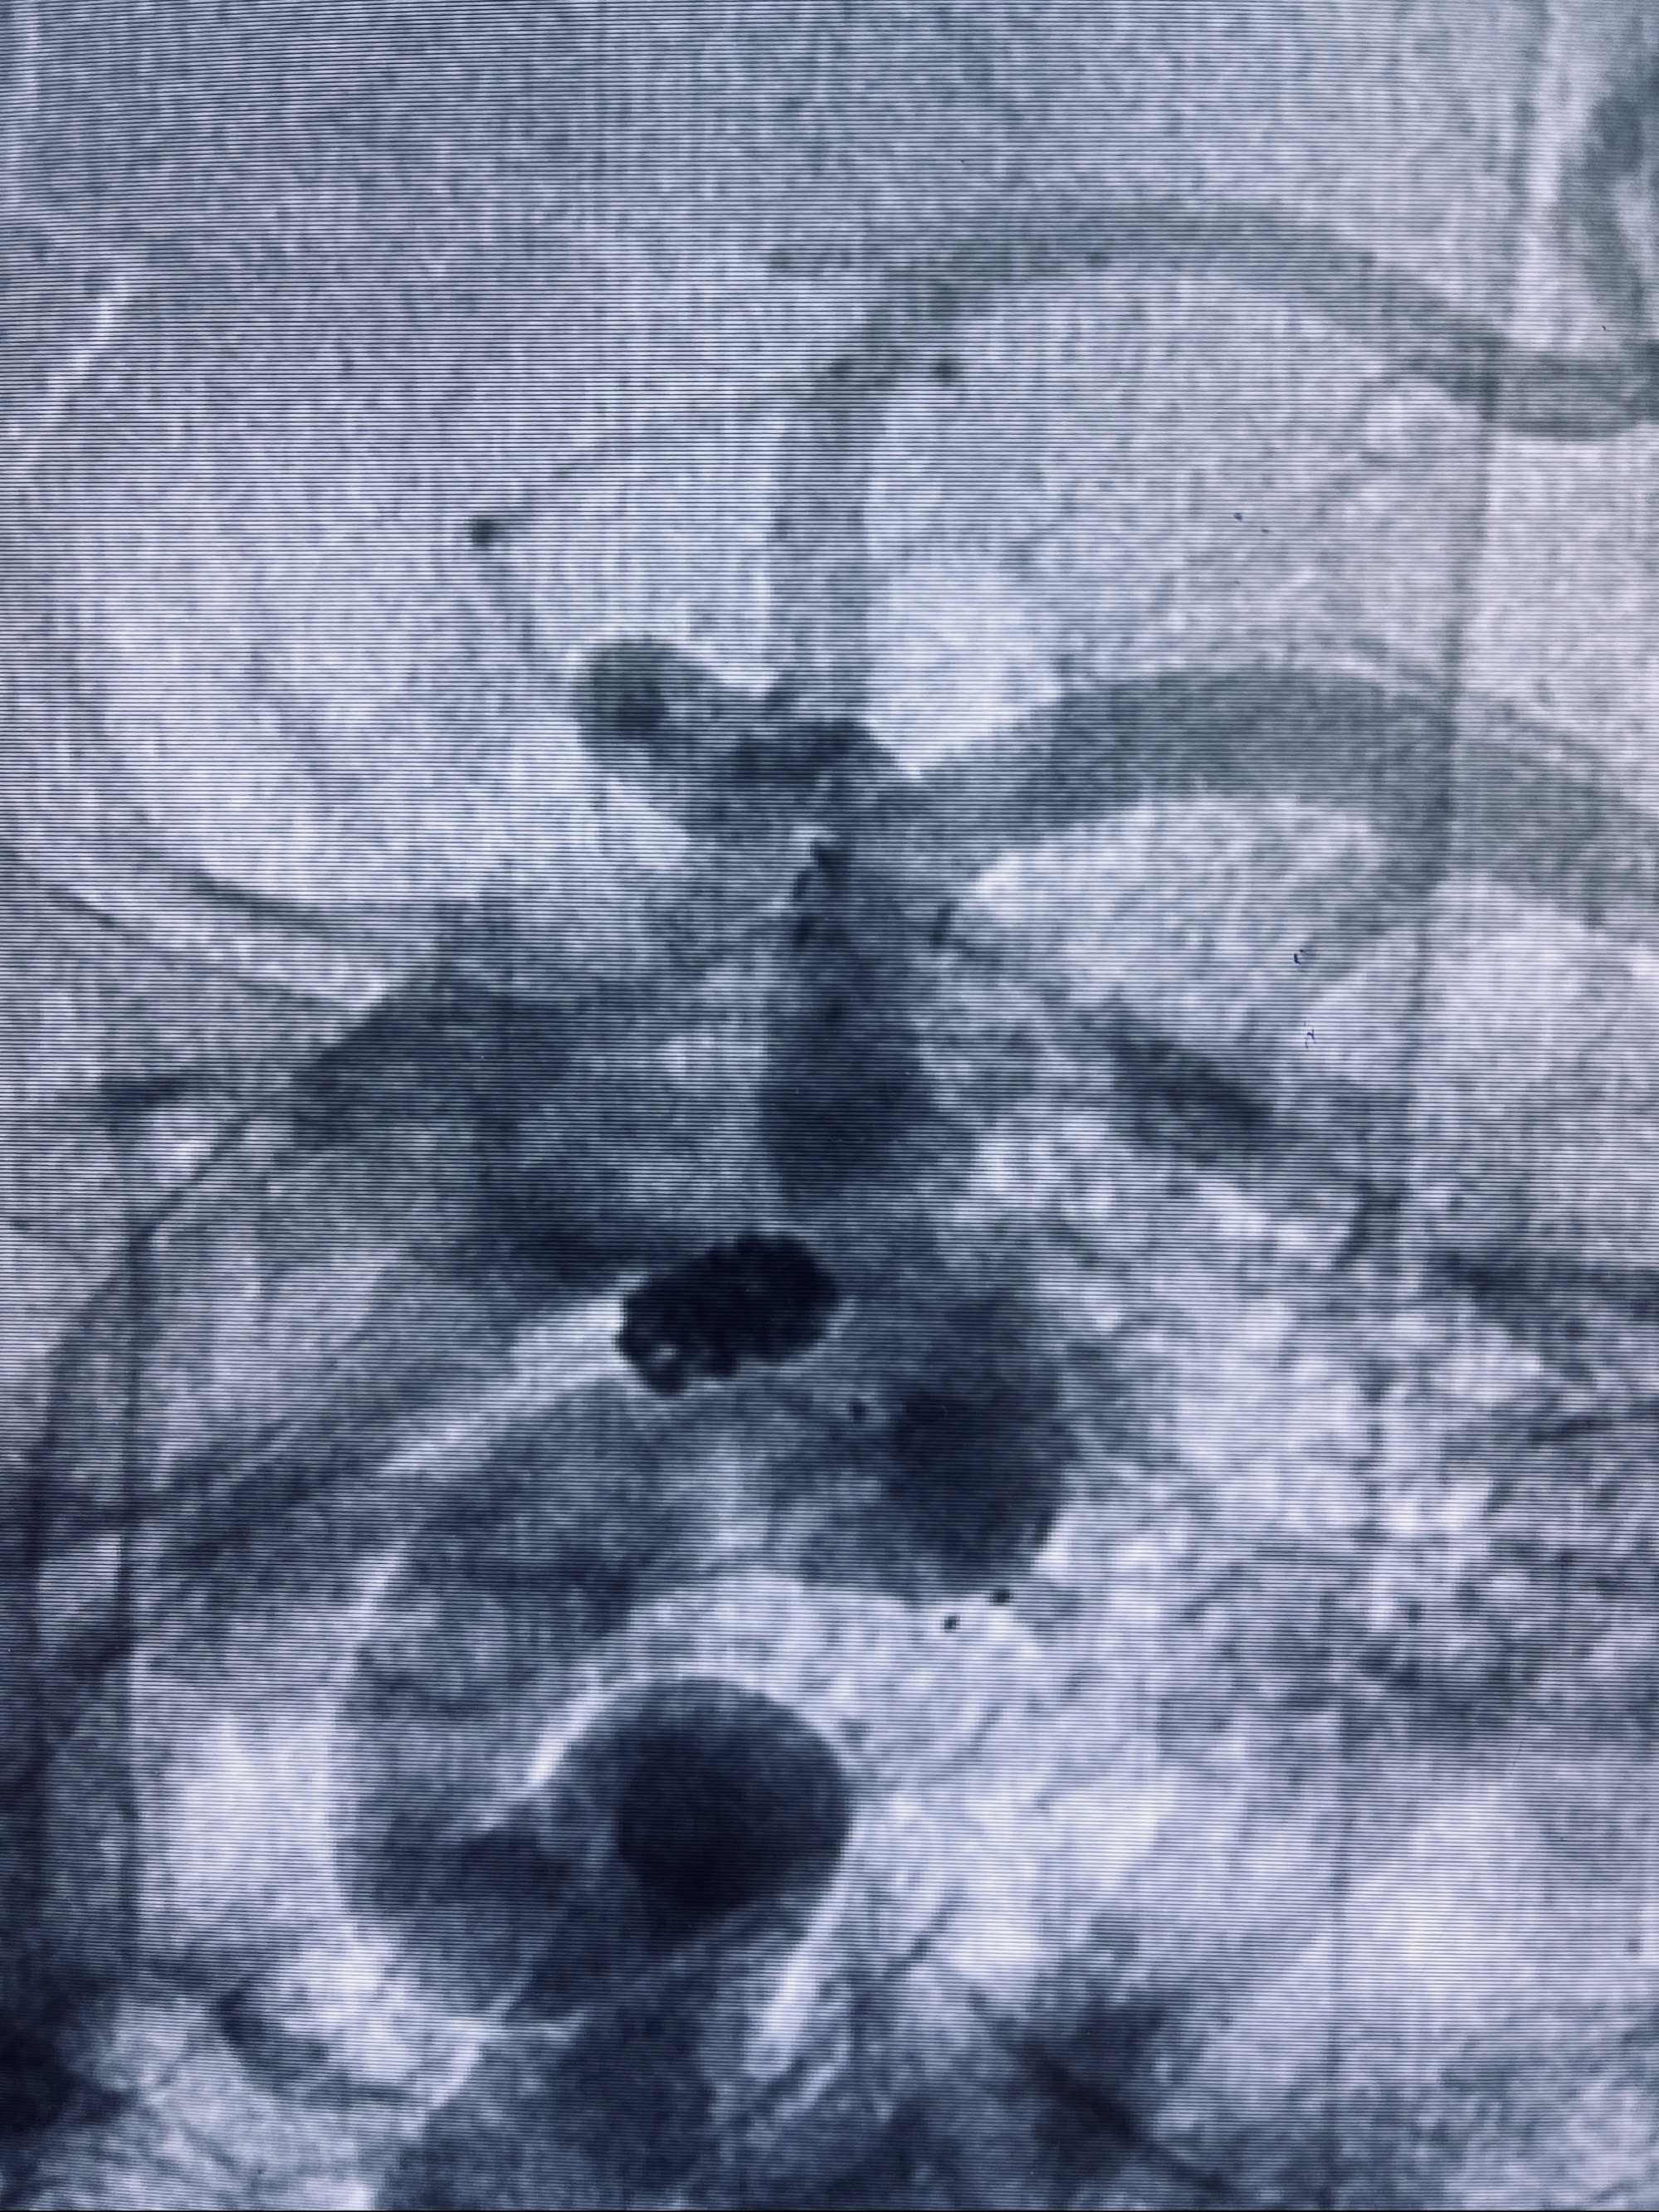

2022-09-29复查DSA

患者支架内血栓,给予阿司匹林+立普妥+依折麦布强化降脂干预